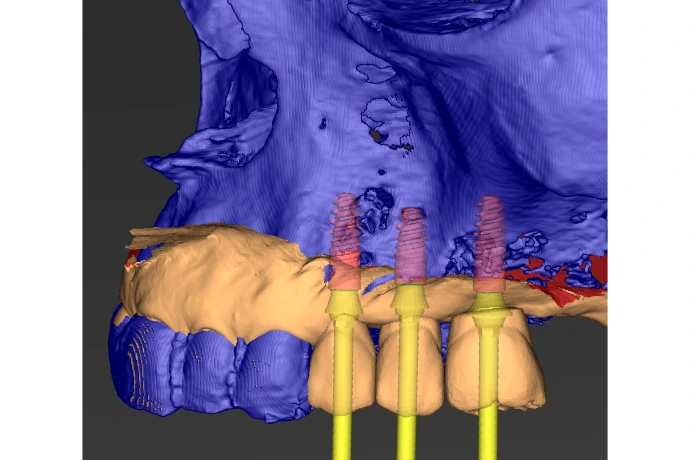

Travaux pratiques : planification (CoDiagnostix) - pose d’implants à main levée et guidée sur différents designs.

Préservation alvéolaire, régénération osseuse simple et optimisation mucogingivale.

Implants Anthogyr, moteurs chirurgicaux, PC avec CodiagnostiX, caméras d’empreinte 3Shape et Straumann, trousses chirurgicales multi-level, modèles pédagogiques, instruments de microchirurgie, membranes collagéniques, xénogreffes et pins.